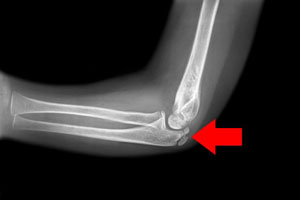

- Elbow Fracture: A fracture is a common injury to the elbow. Elbow fractures may occur from trauma, resulting from various reasons: a fall on an outstretched arm, a direct blow to the elbow, or an abnormal twist to the joint beyond its functional limit. Common elbow fractures include radial head fractures, distal humerus fractures, and olecranon fractures.

- Elbow Dislocation: Elbow dislocation occurs when the bones that make up the joint are forced out of alignment. Elbow dislocations usually occur when you fall onto an outstretched hand during a sporting accident. It can also occur from a traumatic injury such as a motor vehicle accident.

Adolescent elbow injuries are diagnosed with a detailed medical review and thorough physical examination. Your doctor may also order certain imaging studies such as X-rays, MRI, and CT scans for a detailed evaluation of damage to bones and soft tissues of the elbow joint and to confirm the diagnosis.